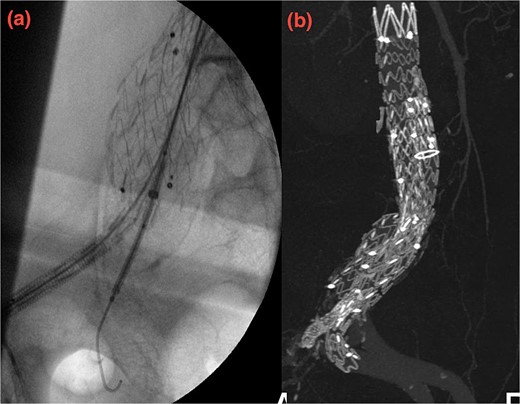

Despite these interventions, the patient experienced further episodes of acute limb ischemia (Fig. 4), leading to thrombolytic therapy a month later. This recurrence prompted a reevaluation of the treatment strategy. We considered extending the graft limb, which would involve sacrificing the hypogastric artery, or using an iliac artery extension with an iliac side branch. We ultimately chose the latter and implanted an E-iliac stent graft (Jotec ISB system) (Fig. 5a and b). Preservation of the hypogastric artery was prioritized, although extending into the external iliac artery would have been a viable alternative. However, the multidisciplinary team decided the preservation of the hypogastric artery would be more appropriate in this patient. The patient was discharged without anticoagulants.

(a, b) Intraoperative images showing implantation of the iliac side branch device ISB.